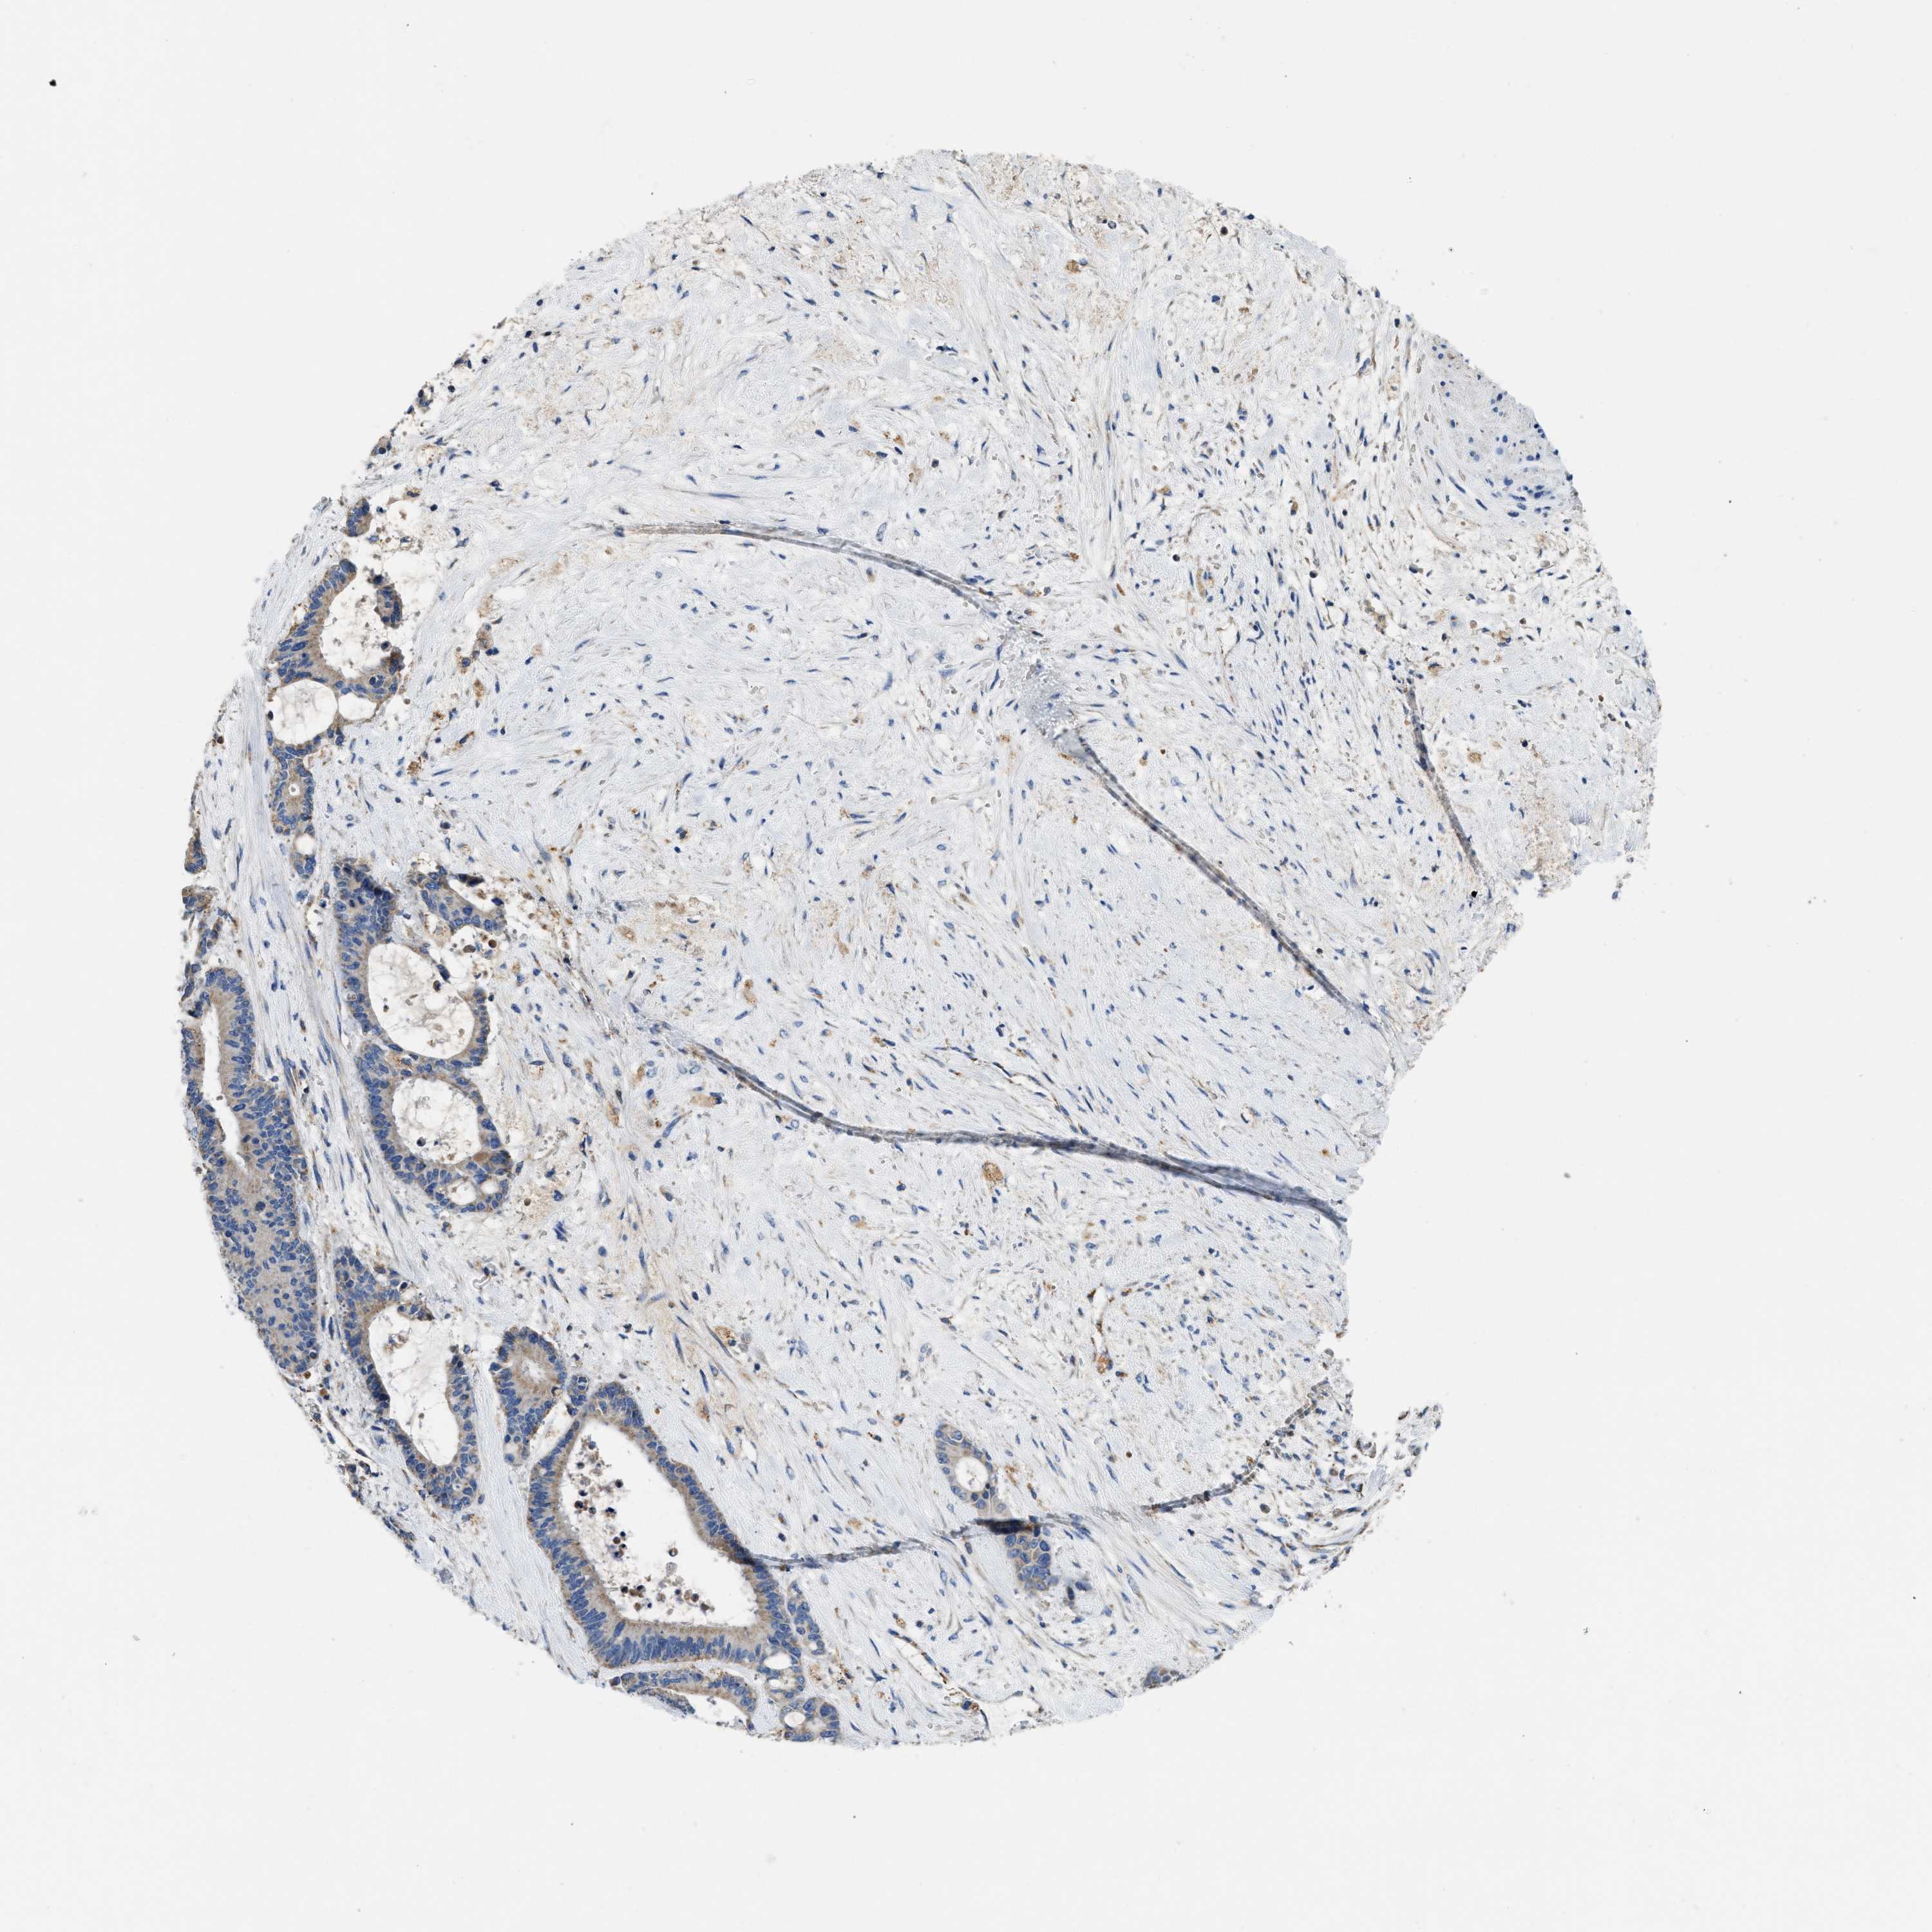

LIVER CANCER - Protein expressioni

A mouse-over function shows sample information and annotation data. Click on an image to view it in a full screen mode. Samples can be filtered based on level of antibody staining by selecting one or several of the following categories: high, medium, low and not detected. The assay and annotation is described here.

Note that samples used for immunohistochemistry by the Human Protein Atlas do not correspond to samples in the TCGA dataset.

Antibody stainingi

Antibody staining in the annotated cell types in the current human tissue is reported as not detected, low, medium, or high, based on conventional immunohistochemistry profiling in selected tissues. This score is based on the combination of the staining intensity and fraction of stained cells.

Each image is clickable and will lead to virtual microscopy that enables deeper exploration of all samples and also displays staining intensity scores, fraction scores and subcellular localization as well as patient and tissue information for each sample.

Antibody HPA018997

Staining

High

Medium

Low

Not detected

Intensity

Strong

Moderate

Weak

Negative

Quantity

>75%

75%-25%

<25%

None

Location

Nuclear

Cytoplasmic/membranous

Cytoplasmic/membranous,nuclear

Cholangiocarcinoma

Carcinoma, Hepatocellular, NOS